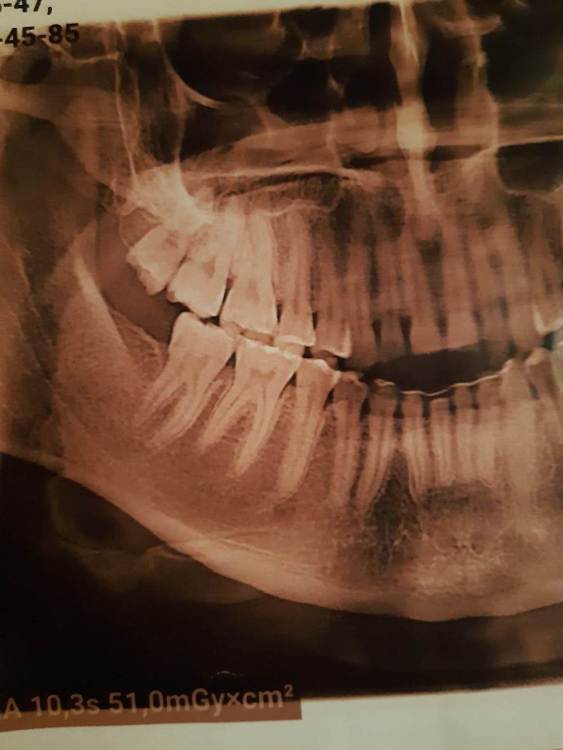

Доброго времени суток, коллеги! Кто может посмотреть КТ, делали по другому поводу, случайно найдено образование. Не беспокоило все это время. На оптг за 2019 год ничего такого не видно. Неужели придется удалять зуб вместе с образованием?

20210401_173901.jpg